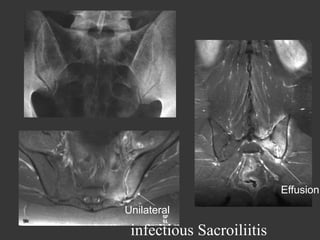

C Noémie

24 year-old

A week after delivery

Inflammatory left buttock pain

infl Sd ++++

C.Noémie

sept 2011

oct 2011

infectious Sacroiliitis staph

Effusion

Unilateral

infectious Sacroiliitis

Infectious sacro-iliitis

•  Unilateral

•  Soft tissus +++

•  Effusion

on X rays and CT scan

Patterns appear later